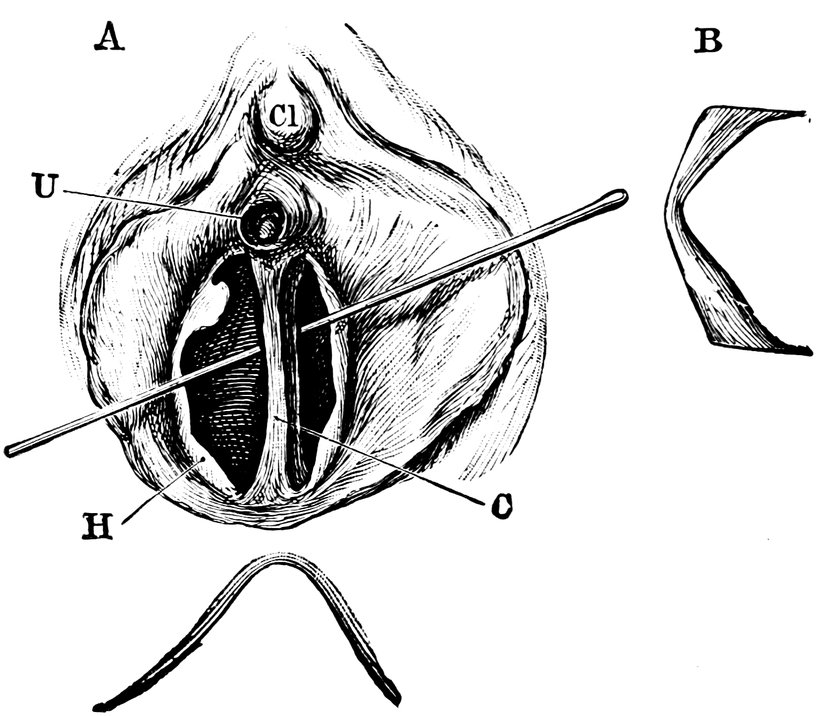

| 41. | A. Septate Hymen in which defloration has been effected through one of the Apertures. U. Urethra. Cl. Clitoris. H. Cicatrized Margin. C. Septum. B. Lateral view of Septum | 70 |